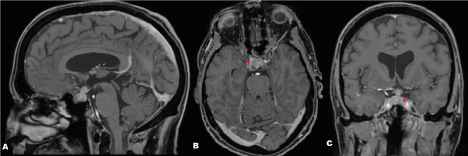

One month after his second PET/CT, and eleven months following his initial presentation, our patient was admitted to hospital with syncope, fatigue and nausea. Investigation revealed hypercortisolism, secondary hypothyroidism, hypogonadal hypogonadism and normal prolactin and growth hormone (Table 1). He was then treated with glucocorticoid, mineralocorticoid, thyroid and testosterone hormone replacement.  He was noted to have polydipsia and polyuria and a clinical diagnosis of diabetes insipidus was made and he was treated with oral desmopressin.  An MRI demonstrated bulky enhancement of the pituitary gland and pituitary infundibulum and marked suprasellar mass-like extension to the suprasellar cistern causing superior displacement and flattening of the optic chiasm (Figure 1). A stereotactic transsphenoidal biopsy of the pituitary gland demonstrated a poorly differentiated squamous cell carcinoma, in keeping with metastasis from a tonsillar primary. After discussion in a multidisciplinary team meeting he commenced stereotactic palliative radiotherapy. During radiotherapy he developed an intermittent left sided 3rd cranial nerve palsy.

Figure 1. Contrast enhanced magnetic resonance imaging scans of sagittal (A), axial (B) and coronal (C) views. Arrows demonstrate mass-like enhancement of pituitary and pituitary stalk with marked suprasellar mass-like extension to the suprasellar cistern causing superior displacement and flattening of the optic chiasm